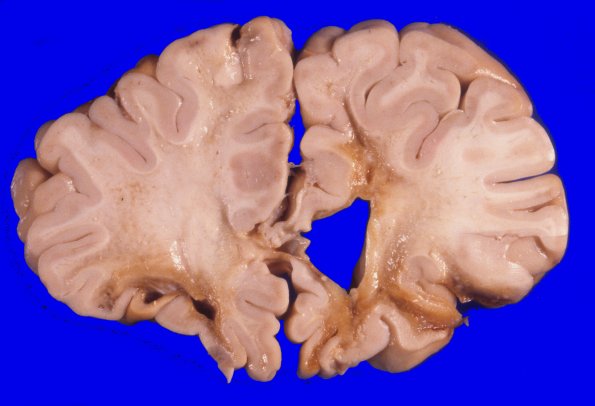

17A3-6 Multiple coronal sections demonstrating many severe contusive injuries with underlying loss of white matter.